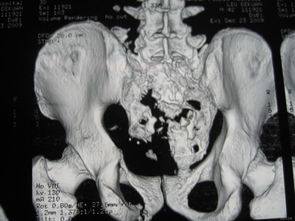

骶尾骨骨折要休息多長時間會好呢,在這期間骨折患者應(yīng)該如何注意自己的飲食呢?那么,請點擊馬上鏈接康復(fù)熱線 骶神經(jīng)損傷嚴(yán)重時可出現(xiàn)跟腱反射消失,但很少出現(xiàn)括約肌功能障礙,予后與神經(jīng)損傷程度有關(guān),輕度損傷予后好,一般一年內(nèi)可望恢復(fù)。